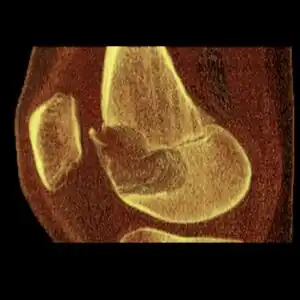

Osteochondroma, a common type of non-cancerous chondrogenic tumors

Osteochondroma[2]